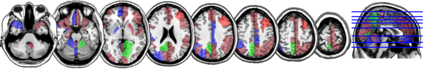

In this paper, we propose methods for functional predictor selection and the estimation of smooth functional coefficients simultaneously in a scalar-on-function regression problem under high-dimensional multivariate functional data setting. In particular, we develop two methods for functional group-sparse regression under a generic Hilbert space of infinite dimension. We show the convergence of algorithms and the consistency of the estimation and the selection (oracle property) under infinite-dimensional Hilbert spaces. Simulation studies show the effectiveness of the methods in both the selection and the estimation of functional coefficients. The applications to the functional magnetic resonance imaging (fMRI) reveal the regions of the human brain related to ADHD and IQ.